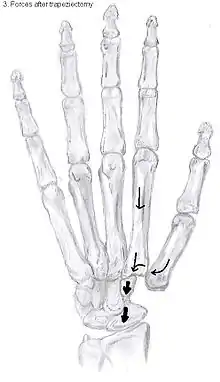

Showing the forces after trapeziectomy

In one randomized trial comparing trapeziectomy alone with trapeziectomy with ligament reconstruction and trapeziectomy with ligament reconstruction and tendon interposition, patients evaluated 5 to 18 years after surgery had similar pain intensity, grip strength and key and tip pinch strengths after each procedure.[29] Trapeziectomy alone is associated with fewer complications than the other procedures.

Trapeziectomy

During trapeziectomy,[30] the trapezium bone is removed without any further surgical adjustments.The trapezium bone is removed through an approximately three centimeter long incision along the lateral side of the thumb. To preserve surrounding structures, the trapezium bone is removed "by splitting" it into pieces.

An empty gap is left by the trapeziectomy and the wound is closed with sutures. Despite this gap, no significant changes in function of the thumb are reported.[27] After the surgery, the thumb will be immobilized with a cast.